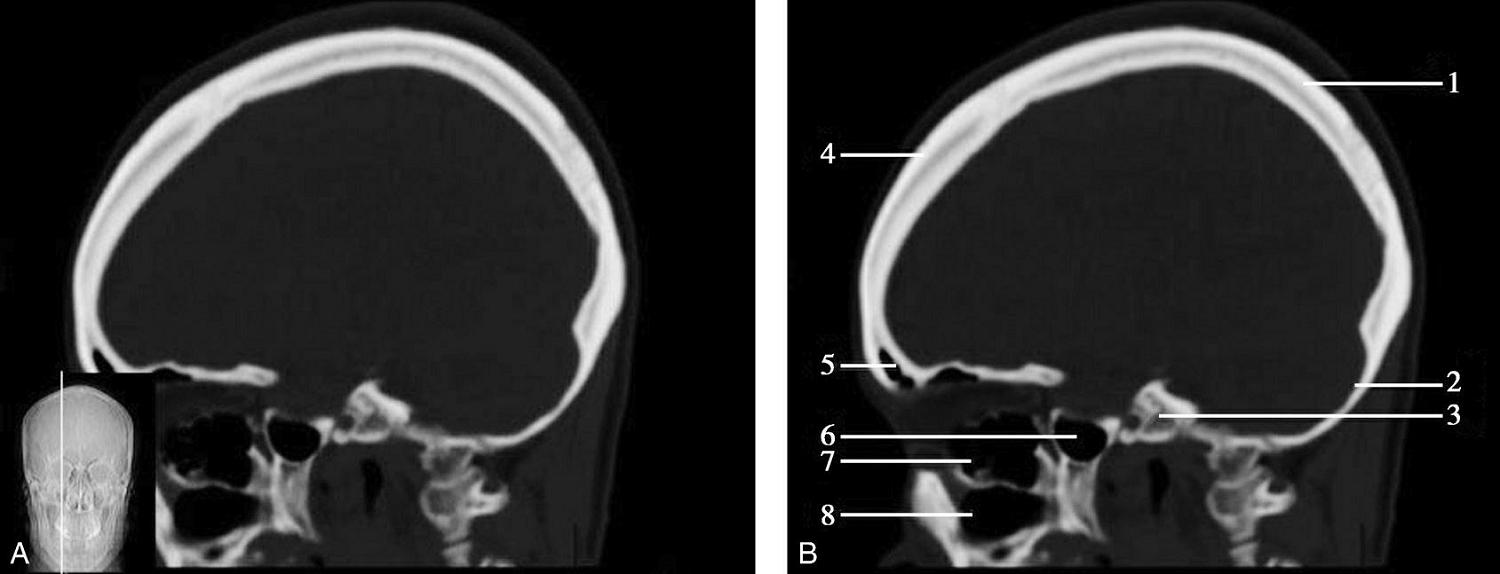

重要结构:胼胝体、垂体、中脑导水管、扣带回、中央沟、第三脑室、斜坡(图1-2-59、图1-2-60)。

图1-2-59 正中矢状面CT

A.矢状面;B.矢状面标注

1.中央沟;2.扣带回;3.胼胝体体部;4.侧脑室;5.中脑;6.胼胝体膝部;7.穹隆;8.第三脑室;9.胼胝体压部;10.垂体;11.中脑导水管;12.第四脑室;13.脑桥;14.蝶窦;15.斜坡;16.小脑扁桃体;17.延髓

图1-2-60 正中矢状面骨窗CT

1.顶骨;2.枕骨;3.斜坡;4.额骨;5.蝶鞍

此层面可显示胼胝体全貌,它位于层面中央区域,是呈上凸下凹的弧形结构,由前向后分为嘴、膝、体和压四部分。扣带回环绕胼胝体上方,扣带沟位于扣带回的上方。大脑半球中部和后部分别可见较深且恒定的中央沟和顶枕沟。中央沟为是额叶顶叶分界标志。

胼胝体下方为侧脑室及穹窿,第三脑室借穹窿与前上方的侧脑室体部分开,背侧丘脑的内侧面以及中脑顶盖分别为第三脑室的外侧壁和底。第三脑室向前籍室间孔与侧脑室相通,向下经中脑导水管通第四脑室。中脑腔狭窄呈管状,即称为中脑导水管,中脑导水管畸形,常见者为导水管的分叉畸形和狭窄,其次可见中脑导水管膈膜,造成先天性脑积水。

脑干由中脑、脑桥和延髓组成,自第三脑室底向下后稍斜行,移行于颈髓。由上至下,脑干腹侧可见脚间池、桥前池和延髓池,脑干背侧可见大脑大静脉池、四叠体池和小脑延髓池。

垂体位于蝶鞍内,其前部为腺垂体,后上部分为神经垂体。垂体下方为鞍底及蝶窦,上缘因鞍膈存在而平直,垂体借垂体柄向上连于丘脑下部。垂体的前上方见视交叉和视束。斜坡作为前颅窝底的重要组成部分与多个重要结构相比邻,矢状位呈三角形,颅内肿瘤或颅外鼻咽部恶性肿瘤均可侵犯至此,原发肿瘤常见为脊索瘤。小脑幕居枕叶和小脑之间,向后下连接窦汇,向前至中脑后方游离,称小脑幕切迹。小脑幕下方为小脑扁桃体。成年人小脑扁桃体下缘由枕骨大孔向下疝入椎管超过5mm称为Chiari畸形,以矢状位显示最佳。